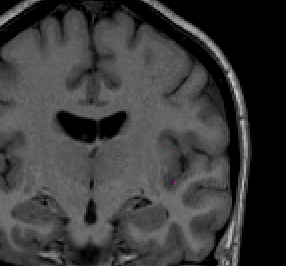

Once you have drawn your sulci lines, the insula should be clearly outlined (by little dots) in the coronal view (Fig 3). This is particularly useful in the more anterior slices.

Figure 3